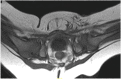

Figure 3.

Immediate post-spica magnetic resonance image after closed reduction revealed a subluxated left hip. Patient treated with subsequent anterior open reduction.